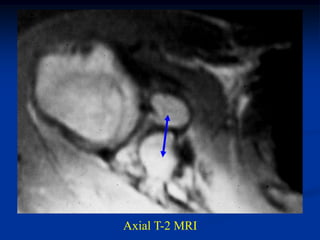

Case #218

58 year female

adamantinoma

proximal tibia

Axial T-2 MRI

Another axial T-2 MRI showing cystic fluid-fluid levels